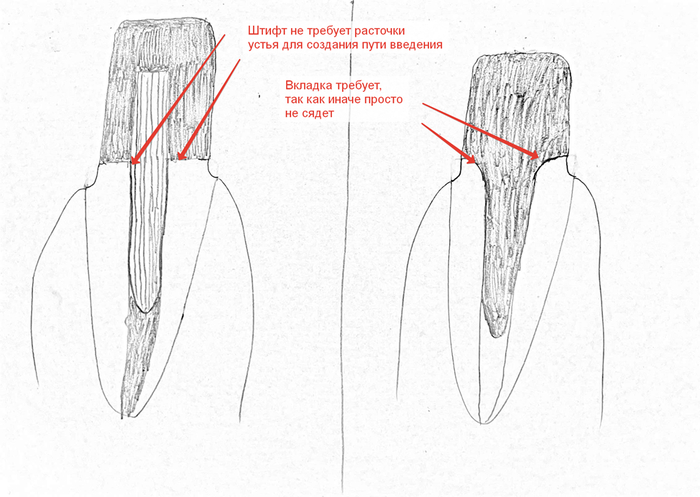

- Лучшая сохранность тканей. Конструкция не требует больше растачивать устье корневого канала, чтобы сделать путь введения конструкции. Штифт адаптируем максимально под канал и заливаем материалом… WIN

- чтобы вставить вкладку нужен путь введения и отсутствие поднутрений. Устье канала должно быть воронкообразное, а для этого надо немного драгоценных тканей зуба. И если на молярах +- 0.5-1 мм не так критичны, то на нижний резцах очень даже.